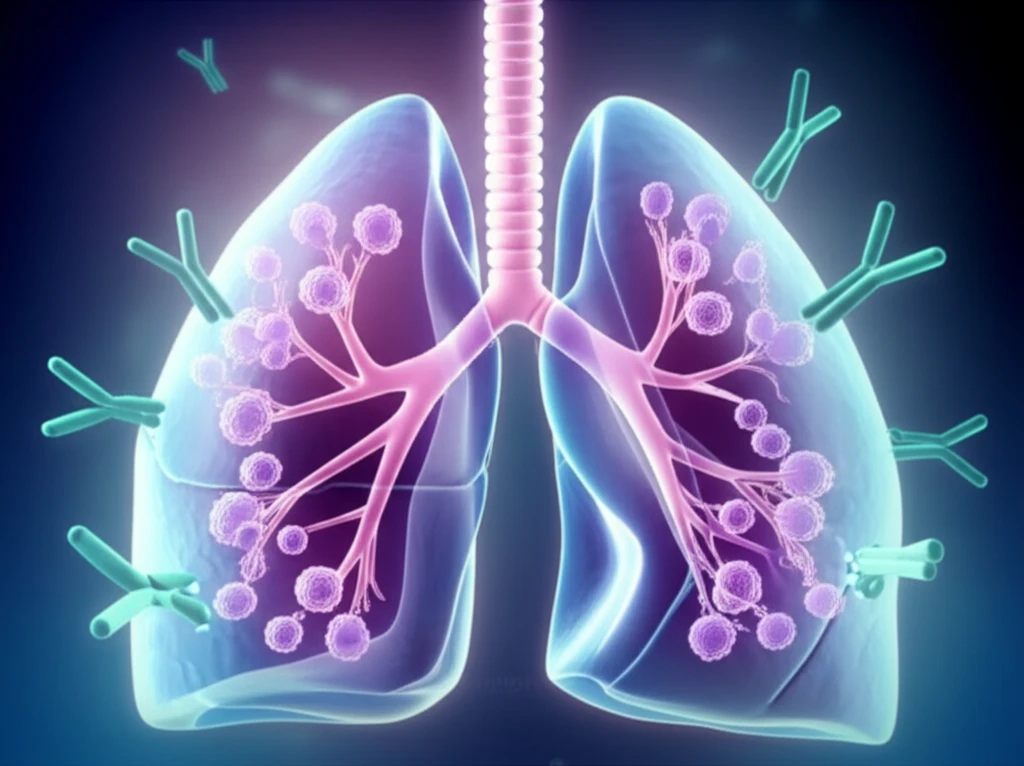

Chronic eosinophilic pneumonia (CEP) is a rare lung condition characterized by an elevated number of eosinophils—a type of white blood cell—in the lungs and bloodstream. This accumulation leads to inflammation and can cause symptoms like cough, shortness of breath, and fatigue. While CEP can affect anyone, it's more commonly diagnosed in middle-aged women, with a significant portion also experiencing asthma.

Now, there's a promising alternative: Anti-IgE therapy. This innovative approach uses recombinant humanized anti-IgE antibodies to target and reduce IgE levels in the body, which in turn helps to decrease eosinophil counts and reduce inflammation. While Anti-IgE therapy has shown success in managing other eosinophil-related conditions like allergic asthma and chronic urticaria, its potential in treating CEP is just beginning to be explored.